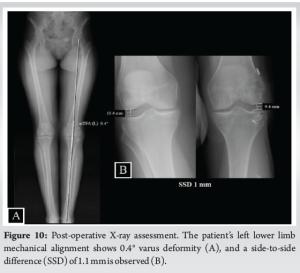

At 24-month follow-up, the operated knee ROM was −5°–130°, with the contralateral knee having −5–135° (Fig. 9). The knee had normal clinical testing for ACL and PLC as well as for the medial collateral ligament (MCL) and posterior cruciate ligament (PCL). However, a side-to-side difference of 1 mm was noted on varus stress X-rays at 20° flexion, but there was symmetry at 0°. The patient was able to return to work as a nurse and to a higher level of sports activity, regularly attending the gym, running on the treadmill and cycling. Tegner, Lysholm, and IKDC subjective scores were 4, 100, and 88.5%, respectively.